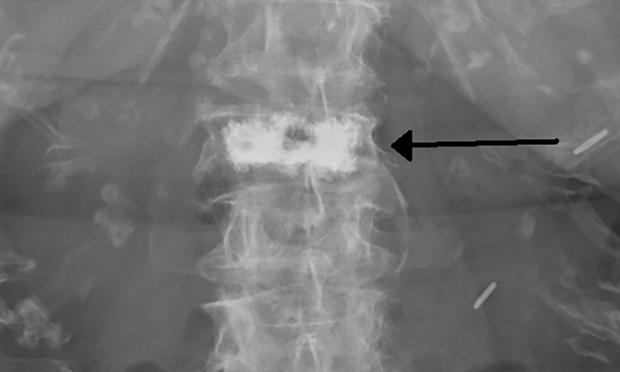

Volume 207, Issue 7: 2 October, 2017. Associate Professor Paul Bird is a rheumatologist in private practice and is also with UNSW Medicine. He discusses the possible resurgence of vertebroplasty as treatment for acute osteoporotic vertebral fractures. With MJA news and online editor, Cate Swannell.